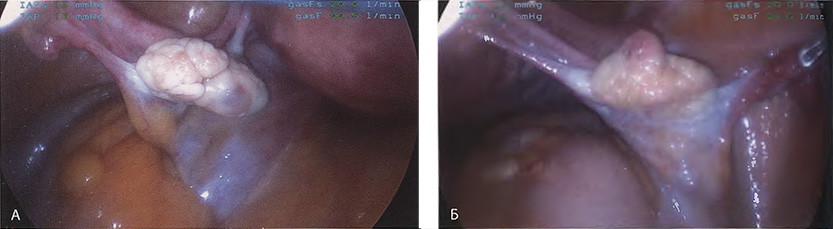

Если оставить в стороне эти достоинства и недостатки, то техника лапароскопической гистерэктомии фактически идентична технике лапаротомической гистерэктомии. В самом начале операции, если она выполняется лапароскопическим методом, необходимо осмотреть всё операционное поле, воспользовавшись для этого панорамным обзором (рис. 12-33—12-37). Операцию начинают с коагуляции и пересечения круглых связок, чем обеспечивается доступ к широкой связке (рис. 12-38—12-40). Брюшину, переходящую с купола мочевого пузыря на переднюю поверхность матки, вскрывают. Пузырь отсепаровывают от матки острым путём (рис. 12-41). После этого вскрывают задний листок широкой связки, а затем принимают решение, оставлять или удалять яичники. Если принято решение оставить яичники, то коагулируют и пересекают собственные связки яичников и маточные трубы (рис. 12-42). Если принято решение удалить яичники (то есть выполнить сальпингоофорэктомию), то с обеих сторон выполняют диссекцию мочеточников от воронко-тазовых связок, которые затем отсепаровывают, коагулируют и пересекают (рис. 12-43). Затем ткань широкой связки отделяют от маточных сосудов (отпрепаровывая их), изолировав, таким образом, мочеточники от маточных сосудов (рис. 12-44 А). Восходящие ветви маточных сосудов коагулируют справа и слева, а затем пересекают (рис. 12-44 Б, В).

Рис. 12-34. А. Увеличенное изображение левого придатка. Б. На левой стороне фотографии видна воронко-тазовая связка.

Рис. 12-35. Вид правого яичника и правой круглой связки.

Рис. 12-36. Панорамный вид мочевого пузыря, правых и левых круглых и широких связок.